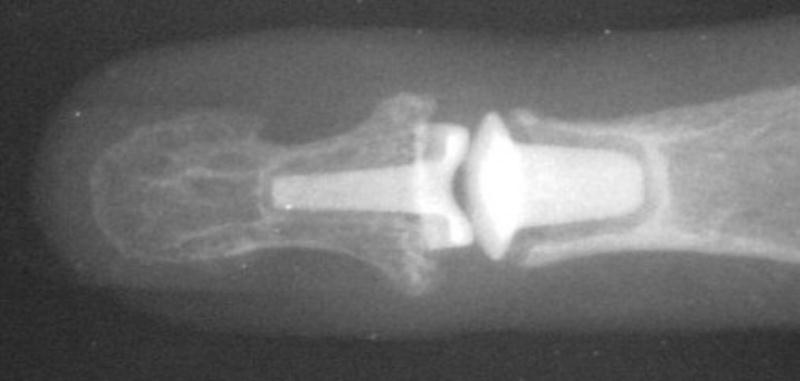

Clinical Example: Distal Interphalangeal Joint Arthroplasty with reversed Ascension carbon implant arthroplasty

These two cases illustrate the use of the Ascension PIP joint implant arthroplasty in the DIP joint position. The stem of the distal component is too wide to fit into the typical distal phalanx, but the proximal component stem will, and in selected cases, the implant will fit in this position if it is placed in a reversed proximal-distal position. These cases illustrate this technique - not as an endorsement, but as a demonstration of  technical feasibility. At one year, each  reconstructed joint was painless and had about 30 degrees range of motion.

Final implant radiographs.